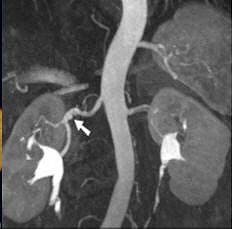

| Coronal oblique 3D volume rendered (above) and thin MIP (below) from CEMRA, in a 60-year-old woman with uncontrolled hypertension, show beaded irregularity involving the distal right renal artery (arrows) consistent with fibromuscular dysplasia (FMD). Images courtesy of Dr. Kambiz Nael. |